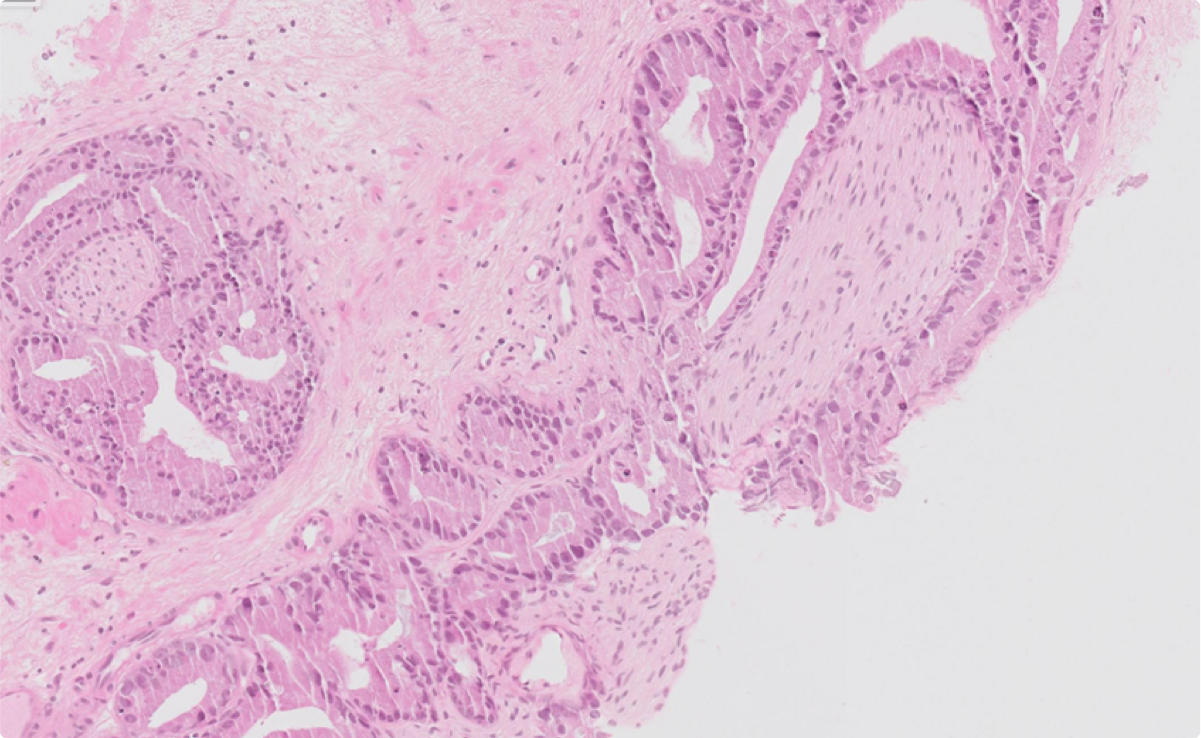

Gleason heatmap

Perineural invasion heatmap